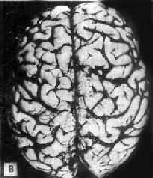

一、Alzheimer病Alzheimer病又称初老期痴呆,是以进行性痴呆为主要临床表现的大脑变性性疾病,起病多在50岁以后。随着人类寿命的延长,本病的发病率呈增高趋势。按照美国的诊断标准,上海60岁以上人群发病率为3.46%。65岁以上人群为4.61%。临床表现为进行性精神状态衰变,包括记忆、智力、定向、判断能力、情感障碍和行为失常甚至发生意识模糊等。患者通常在发病后5~6年内死于继发感染和全身衰竭。 【病理变化】 肉眼观,脑萎缩明显,脑回窄、脑沟宽,病变以额叶、顶叶及颞叶最显着(图16-32),脑切面可见代偿性脑室扩张。

图16-32 初老期痴呆的脑 示脑明显萎缩(A),与正常脑(B)的对比 镜下,本病最主要的组织病变有:老年斑,神经原纤维缠结,颗粒空泡变性,Hirano小体等。 (1)老年斑:为细胞外结构,直径为20~150μm,最多见于内嗅区皮质、海马CA-1区,其次为额叶和顶叶皮质。银染色显示,斑块中心为一均匀的嗜银团,刚果红染色呈阳性反应,提示其中含淀粉样蛋白,其中含该蛋白的前体β/A-4蛋白及免疫球蛋白成分。中心周围有空晕环绕,外围有不规则嗜银颗粒或丝状物质。电镜下可见该斑块主要由多个异常扩张变性之轴索突触终末构成(图16-33)。